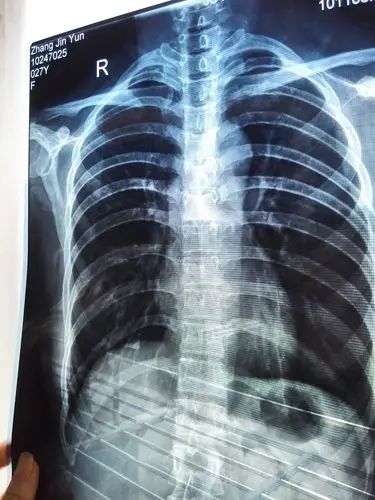

肋骨骨折左侧1-4,右侧5-9,一个半月,之前已经不疼了,这两天稍微活动下

胸部外伤,肋骨骨折,大家看是第几根?

病例24肋骨骨折

多发性肋骨骨折